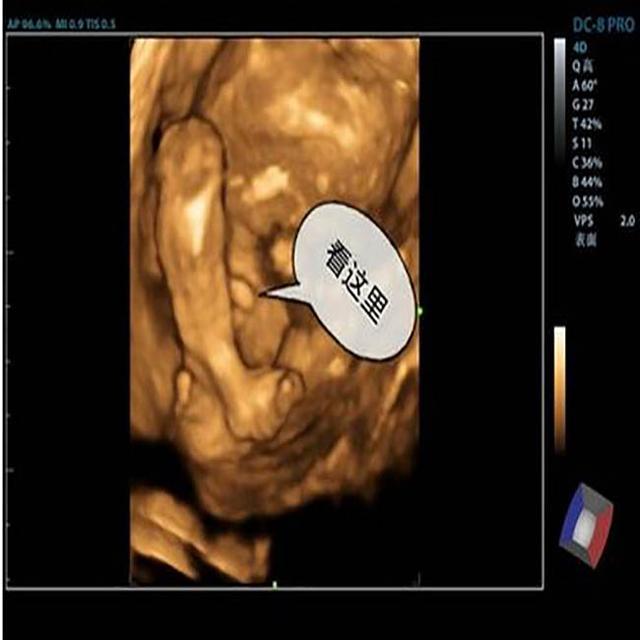

第一胎是女儿 , 在二胎做产检时 , 医生说好 , 意思二胎要么是男孩 , 和第一胎的女儿合成一个“好”字 , 也可以理解为第二胎同样是个女孩 , 意思是医生的话里透露着对第一胎是女孩的事情的认同 , 其实医生的话是模棱两可 , 胎儿是男是女 , 只有帮做产检的医生知道 , 将来不管孕妇生下来的是男孩还是女孩 , 医生都可以根据结果给你做出合理的解释 。

随着社会的发展与进步 , 现在跟以前相比 , 有不少地方还是重男轻女 , 想千方百计地在孩子未出世之前 , 鉴定宝宝的性别 , 而在我们中国 , 医院是严禁鉴定胎儿性别的 , 但每天做产检的人那么多 , 依旧有不少人在做产检时 , 想通过跟医生的聊天内容里 , 找到能辨别宝宝性别的蛛丝马迹 , 既是国家明令禁止的事情 , 医生也不会触其律条 , 知法犯法 , 直接告诉你胎儿性别的 , 但又不想被投诉 , 只好回答得模棱两可 。